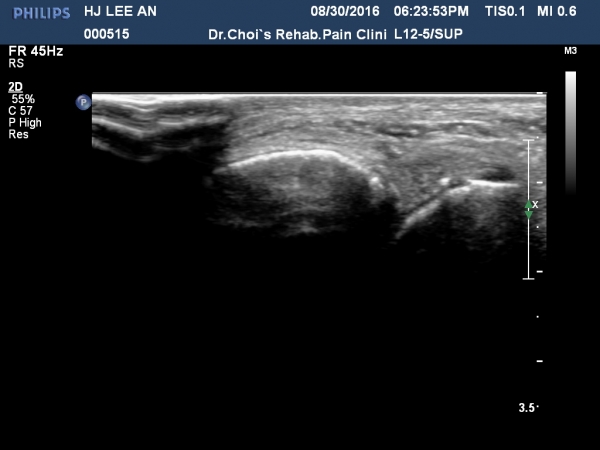

Àü°ÅºñÀδë Á¾´Ü¸é°Ë»ç¿¡¼­ ÀδëÀÇ Àú¿¡ÄÚ ºÎÁ¾ÀÌ °üÂûµÇ³ª °ß¿­°ñÀýÀº °üÂûµÇÁö ¾ÊÀ½(»çÁø 4, 5, 6, 7)

Àü°ÅºñÀδë ÃÊÀ½ÆÄÀ¯µµÇÏ ºÎÇϰ˻翡¼­ ÀδëÀÇ ºñ°ñºÎÂøºÎ¿¡¼­ Àδë¿Í ºÎÂøµÈ °ñÆíÀÇ ÀÌÅ»ÀÌ

°üÂûµÊ(÷ºÎµ¿¿µ»ó).